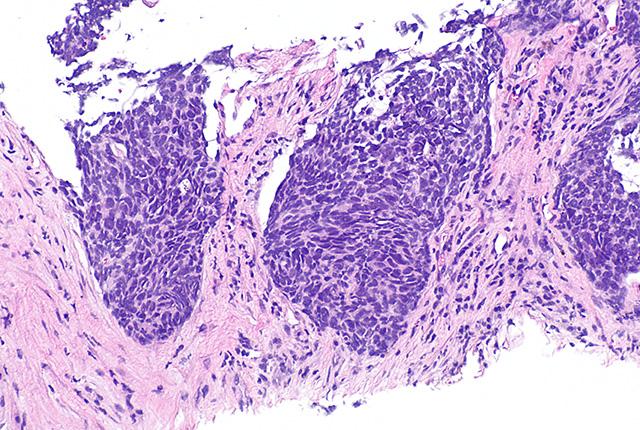

Standard care for stage III non-small cell lung cancer is radiotherapy and concurrent chemotherapy. Even so, approximately 50% of patients experience tumor recurrence within the radiotherapy field. Reducing such “local” recurrences has been shown to enhance survival of these patients, and radiation oncologists are focused on improving radiotherapy’s tumor control.

Radiotherapy damages the DNA within tumor cells, rendering them unable to replicate. But all cells, including cancer cells, have great capacity to repair DNA damage because DNA is so important to cells’ survival, Rengan said.

Nelfinavir, a protease inhibitor, was first used in 1997 to treat HIV patients. More recently, though, nelfinavir has been shown to shut down the DNA repair mechanisms within tumor cells. That effect led Rengan and colleagues to examine whether Nelfinavir might make cancer cells more vulnerable to radiotherapy, resulting in better patient outcomes.